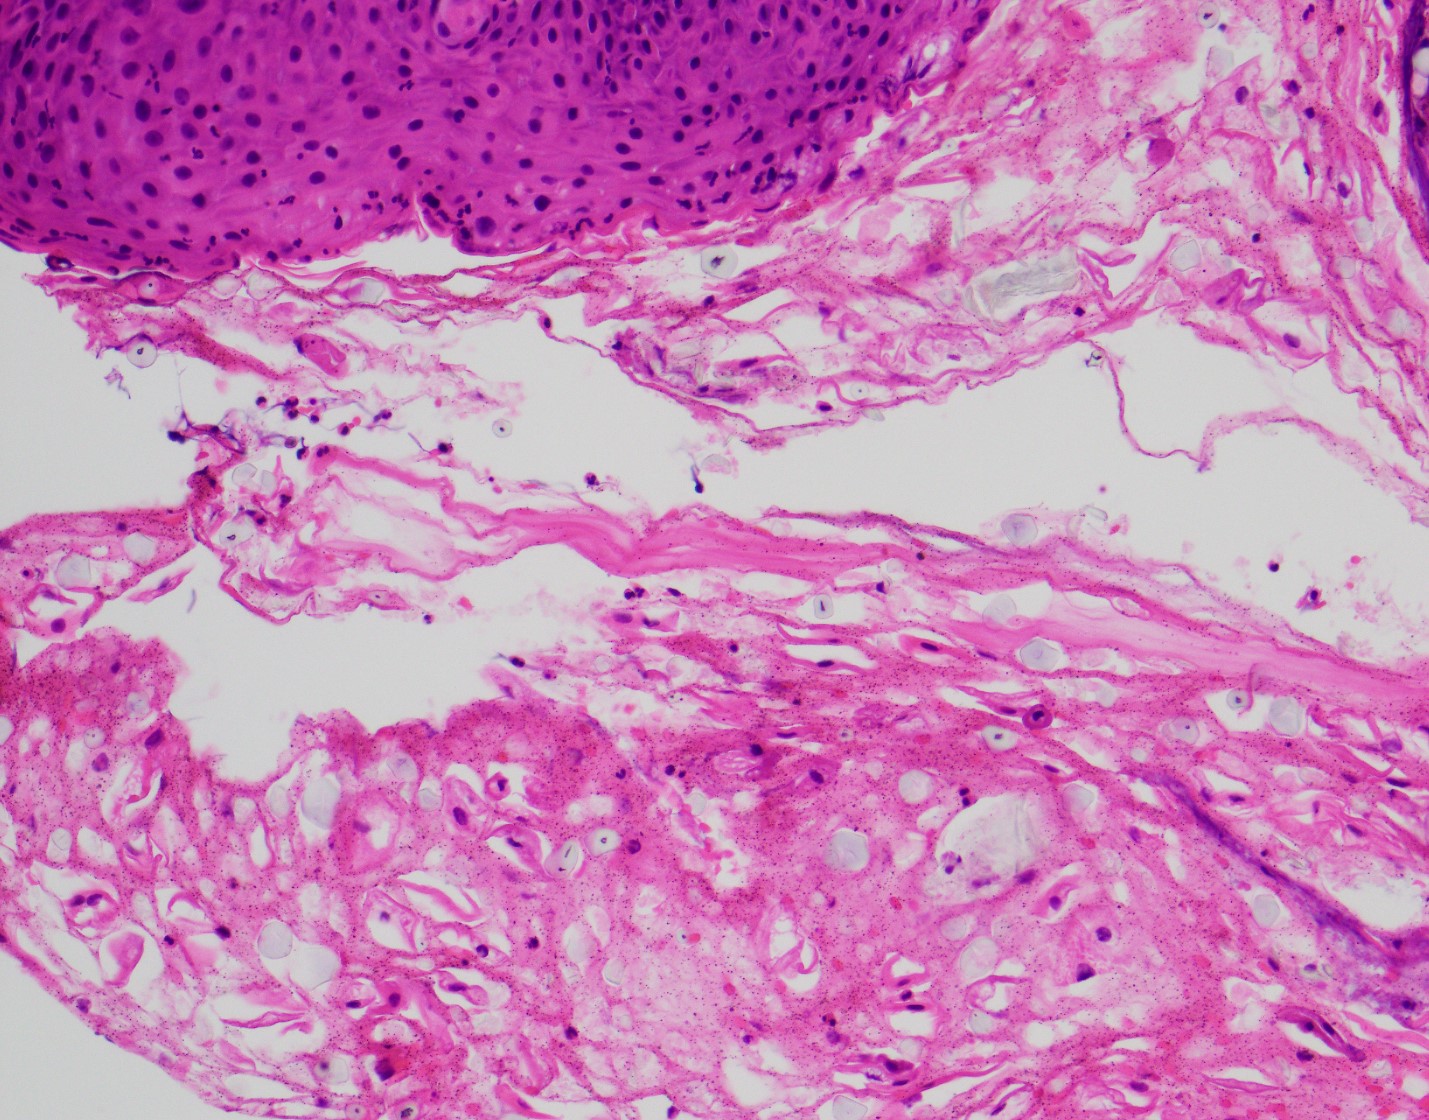

A 64 year-old man with history of clear cell renal cell carcinoma s/p nephrectomy (2021) presents with scrotal pain and firmness. Ultrasound reveals a 2 cm solid lesion. Serum tumor markers (hCG and AFP) were normal. The tumor was negative for SALL4, OCT3/4, AFP, and showed focal patchy positivity for pancytokeratin (focal). PAX8 was weakly positive. Additional stains are displayed in the pictures.